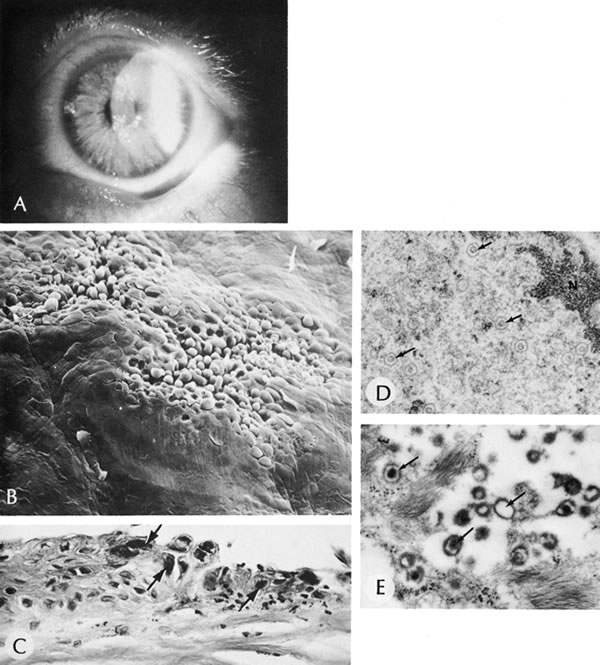

56. Polack F, Graue E: Scanning electron microscopy of congenital corneal

leukomas (Peters' anomaly). Am J Ophthalmol 88:169, 1979.

57. Kuper C, Kuwabara K, Stark W: The histopathology of Peters' anomaly.

Am J Ophthalmol 80:653, 1975.

58. Lee C, Yue B, Robin J: Immunohistochemical studies of Peters' anomaly.

Ophthalmology 96:958, 1989.